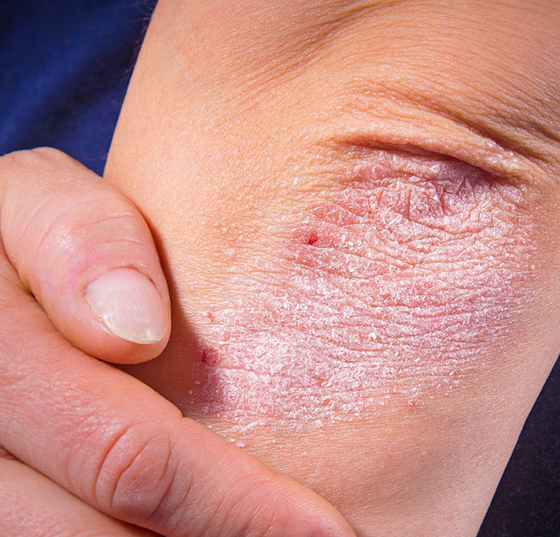

• Psoriasis vulgaris

Patientenadaptierte Biologika-Therapie – Was sagt die neue S3-Leitlinie dazu?

Hervorzuheben ist das Update der Empfehlungen zur Durchführung der Systemtherapie. Dabei wurden neu zugelassene Wirkstoffe integriert, ausserdem gilt ein spezieller Fokus der Berücksichtigung von Komorbiditäten und besonderen Behandlungssituationen. Zu den...…